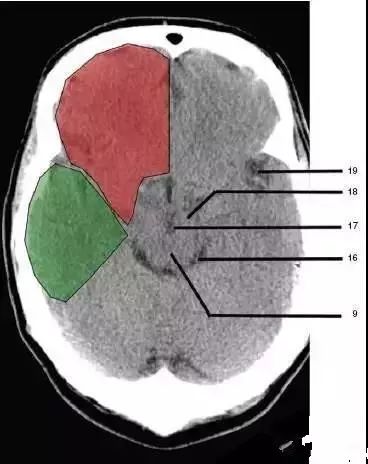

10、垂体窝(Pituitary fossa):绿色部分为颞叶(Temporal Lobe),浅红色部分为额叶(Frontal Lobe)

16、环池(Ambient cistern)

17、角间池 (Interpeduncular cistern)

18、大脑角(Cerebral peduncle)

19、侧裂池(Sylvian fissure):绿色部分为颞叶(Temporal Lobe),浅红色部分为额叶(Frontal Lobe)